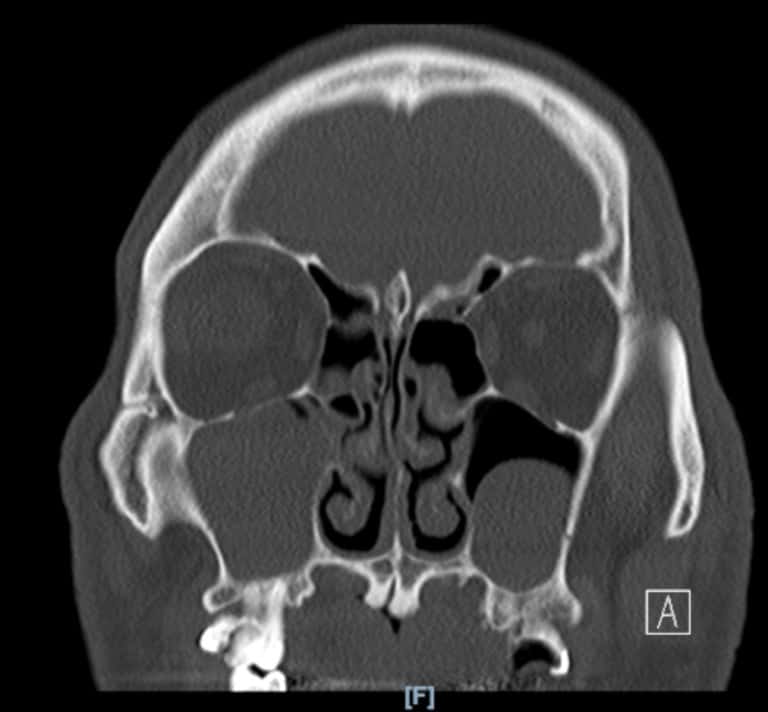

Imaging

A computed tomography (CT) scan to better understand what happens inside their sinuses.